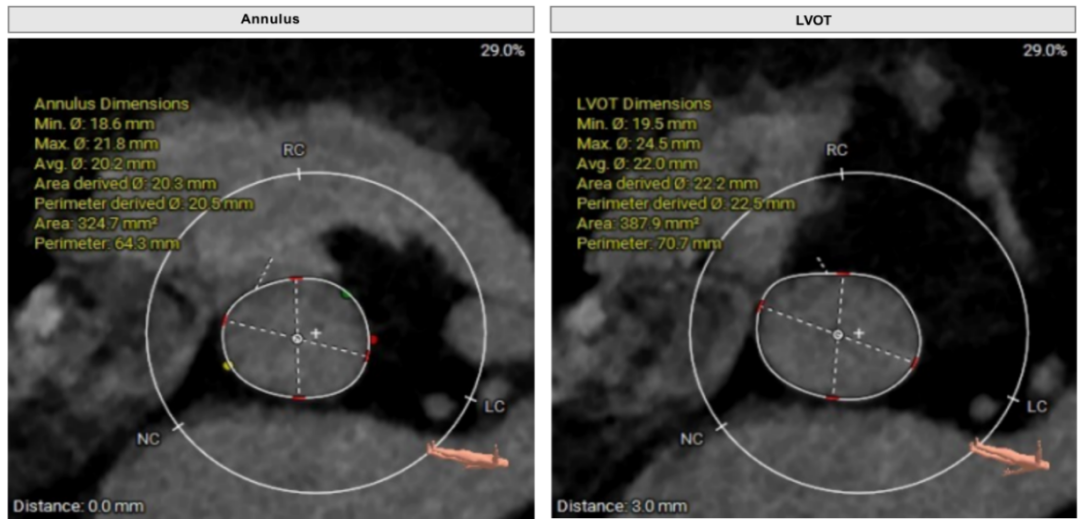

术前CT评估

①Type1二叶瓣,瓣环较小,无窦较大,左右窦有明显瓣叶融合脊;

②瓣叶增厚,瓣口打开受限;

③整体无钙化,AR为主。

瓣上分析

3) 根据瓣环瓣上测量结果,综合评定不预扩张,预装TaurusElite26瓣膜;沛嘉2代输送器非常柔顺,有利于跨过扭曲的主动脉弓部;

4) 释放采用左右重合体位,瓣下2mm释放,结合多体位术中进一步评估瓣膜深度;